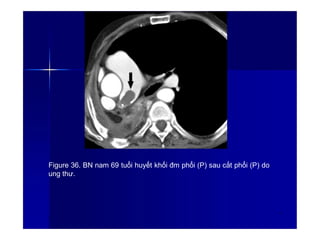

Figure 36. BN nam 69 tuổi huyết khối đm phổi (P) sau cắt phổi (P) do

ung thư.

5